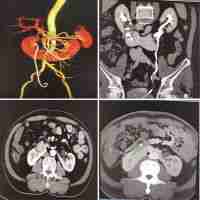

| Abstract | We reported a case of pure laparoscopic radical nephroureterectomy for complicated renal pelvis carcinoma combined with horseshoe kidney (HSK). The aim was to present a case report and review of the literature about renal pelvis carcinoma combined with HSK. The case report includes a history of patient data. The pure laparoscopic radical nephroureterectomy was provided with the informed consent of the patient. A 53-year-old patient was diagnosed with a right renal pelvis mass with HSK. We performed laparoscopic radical nephroureterectomy with partial cystectomy and horseshoe renal isthmus amputation. Histopathological features, computed tomography urography (CTU), and angiography (CTA) confirmed the diagnosis of renal pelvis carcinoma combined with HSK. The tumor was removed, and the patient made an uneventful recovery. Renal pelvis carcinoma combined with HSK is a rare case. Due to severe anatomical abnormalities, this disease is a major challenge for urologists. We share our successful case for readers to learn from. |